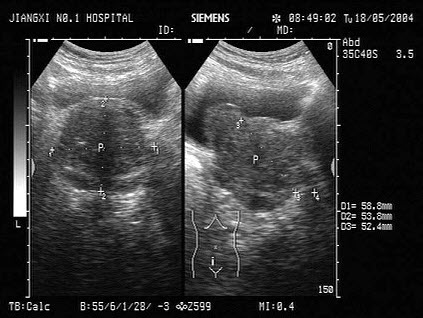

50、单项选择题

男性,65岁,排尿困难,尿线细,滴淋,尿后不尽感等症状,如图所示。最可能的诊断为()